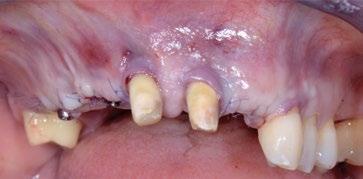

Se presenta el caso de un paciente varón de 48 años de edad, ASA II, fumador que acude a consulta por la pérdida de su incisivo central superior derecho (Figura 1).

A la exploración clínica se observa enfermedad periodontal estadio III grado B con múltiples ausencias dentarias posteriores de larga evolución que han ocasionado la migración de los dientes adyacentes y antagonistas generando múltiples prematuridades e interferencias. Como consecuencia de todo ello, el paciente ha perdido el diente 1.1 con pérdida de volumen de tejido y el 2.1 presenta movilidad grado III con pronóstico imposible (Figura 2).

En la exploración radiográfica en 3D (CBCT) se aprecia ausencia de cortical vestibular en 2.1 y un defecto óseo horizontal en 1.1 (Figura 3).

Se planifica tratamiento periodontal para estabilizar la situación de partida, (se recomienda tratamiento de ortodoncia que el paciente declina) exodoncia del diente 2.1, legrado minucioso del proceso periodontal asociado, colocación de dos implantes Prama Long neck de manera simultánea a la exodoncia, regeneración ósea guiada de ambos defectos mediante abordaje en tunel, compensación de la pérdida de volumen mediante la colocación de tejido conec?vo de paladar a través del mismo acceso y consecución de estética inmediata por medio de provisionales atornillados que guíen la cicatrización en forma y posición.